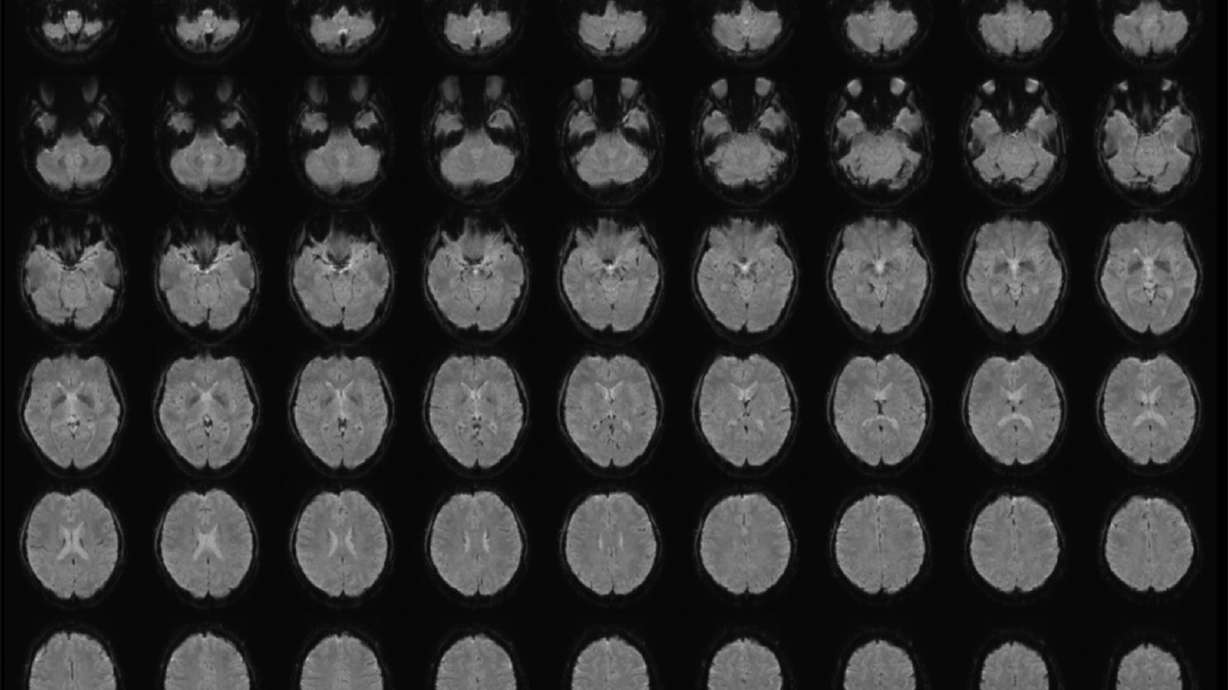

Horikawa, a researcher at telecommunication company NTT's Communication Science Laboratories just outside Tokyo, began by analyzing the brain activity of four men and two women, native Japanese speakers between 22 and 37 years old, scanning their brains as they watched video clips. The participants viewed 2,180 videos without sound that were seconds long and varied in content among objects, scenes and actions.